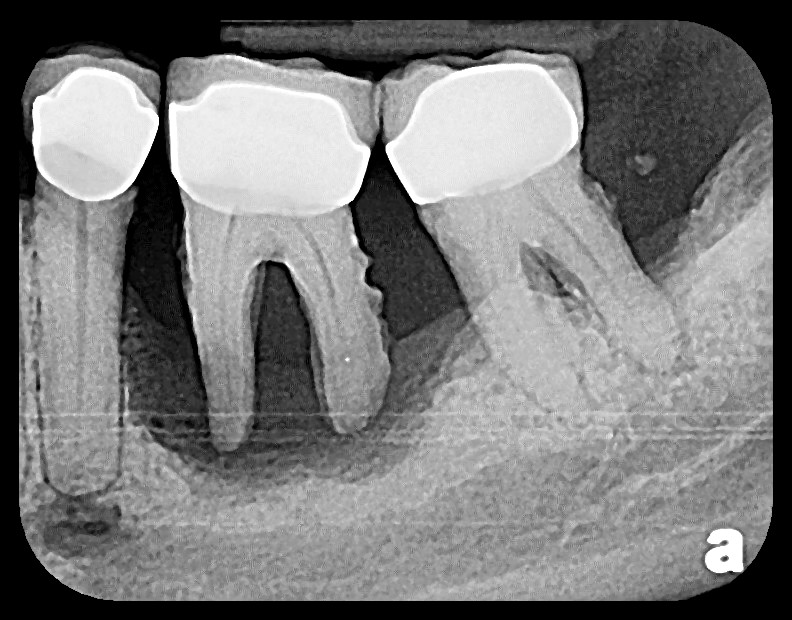

X-RAY TAKEN BEFORE IMPLANTS, HOPELESS TEETH

Implant and restorative dental case at Britten Periodontics and Implant Dentistry in Clearwater, Florida, showcasing successful tooth replacement and restoration for improved oral health and aesthetics.